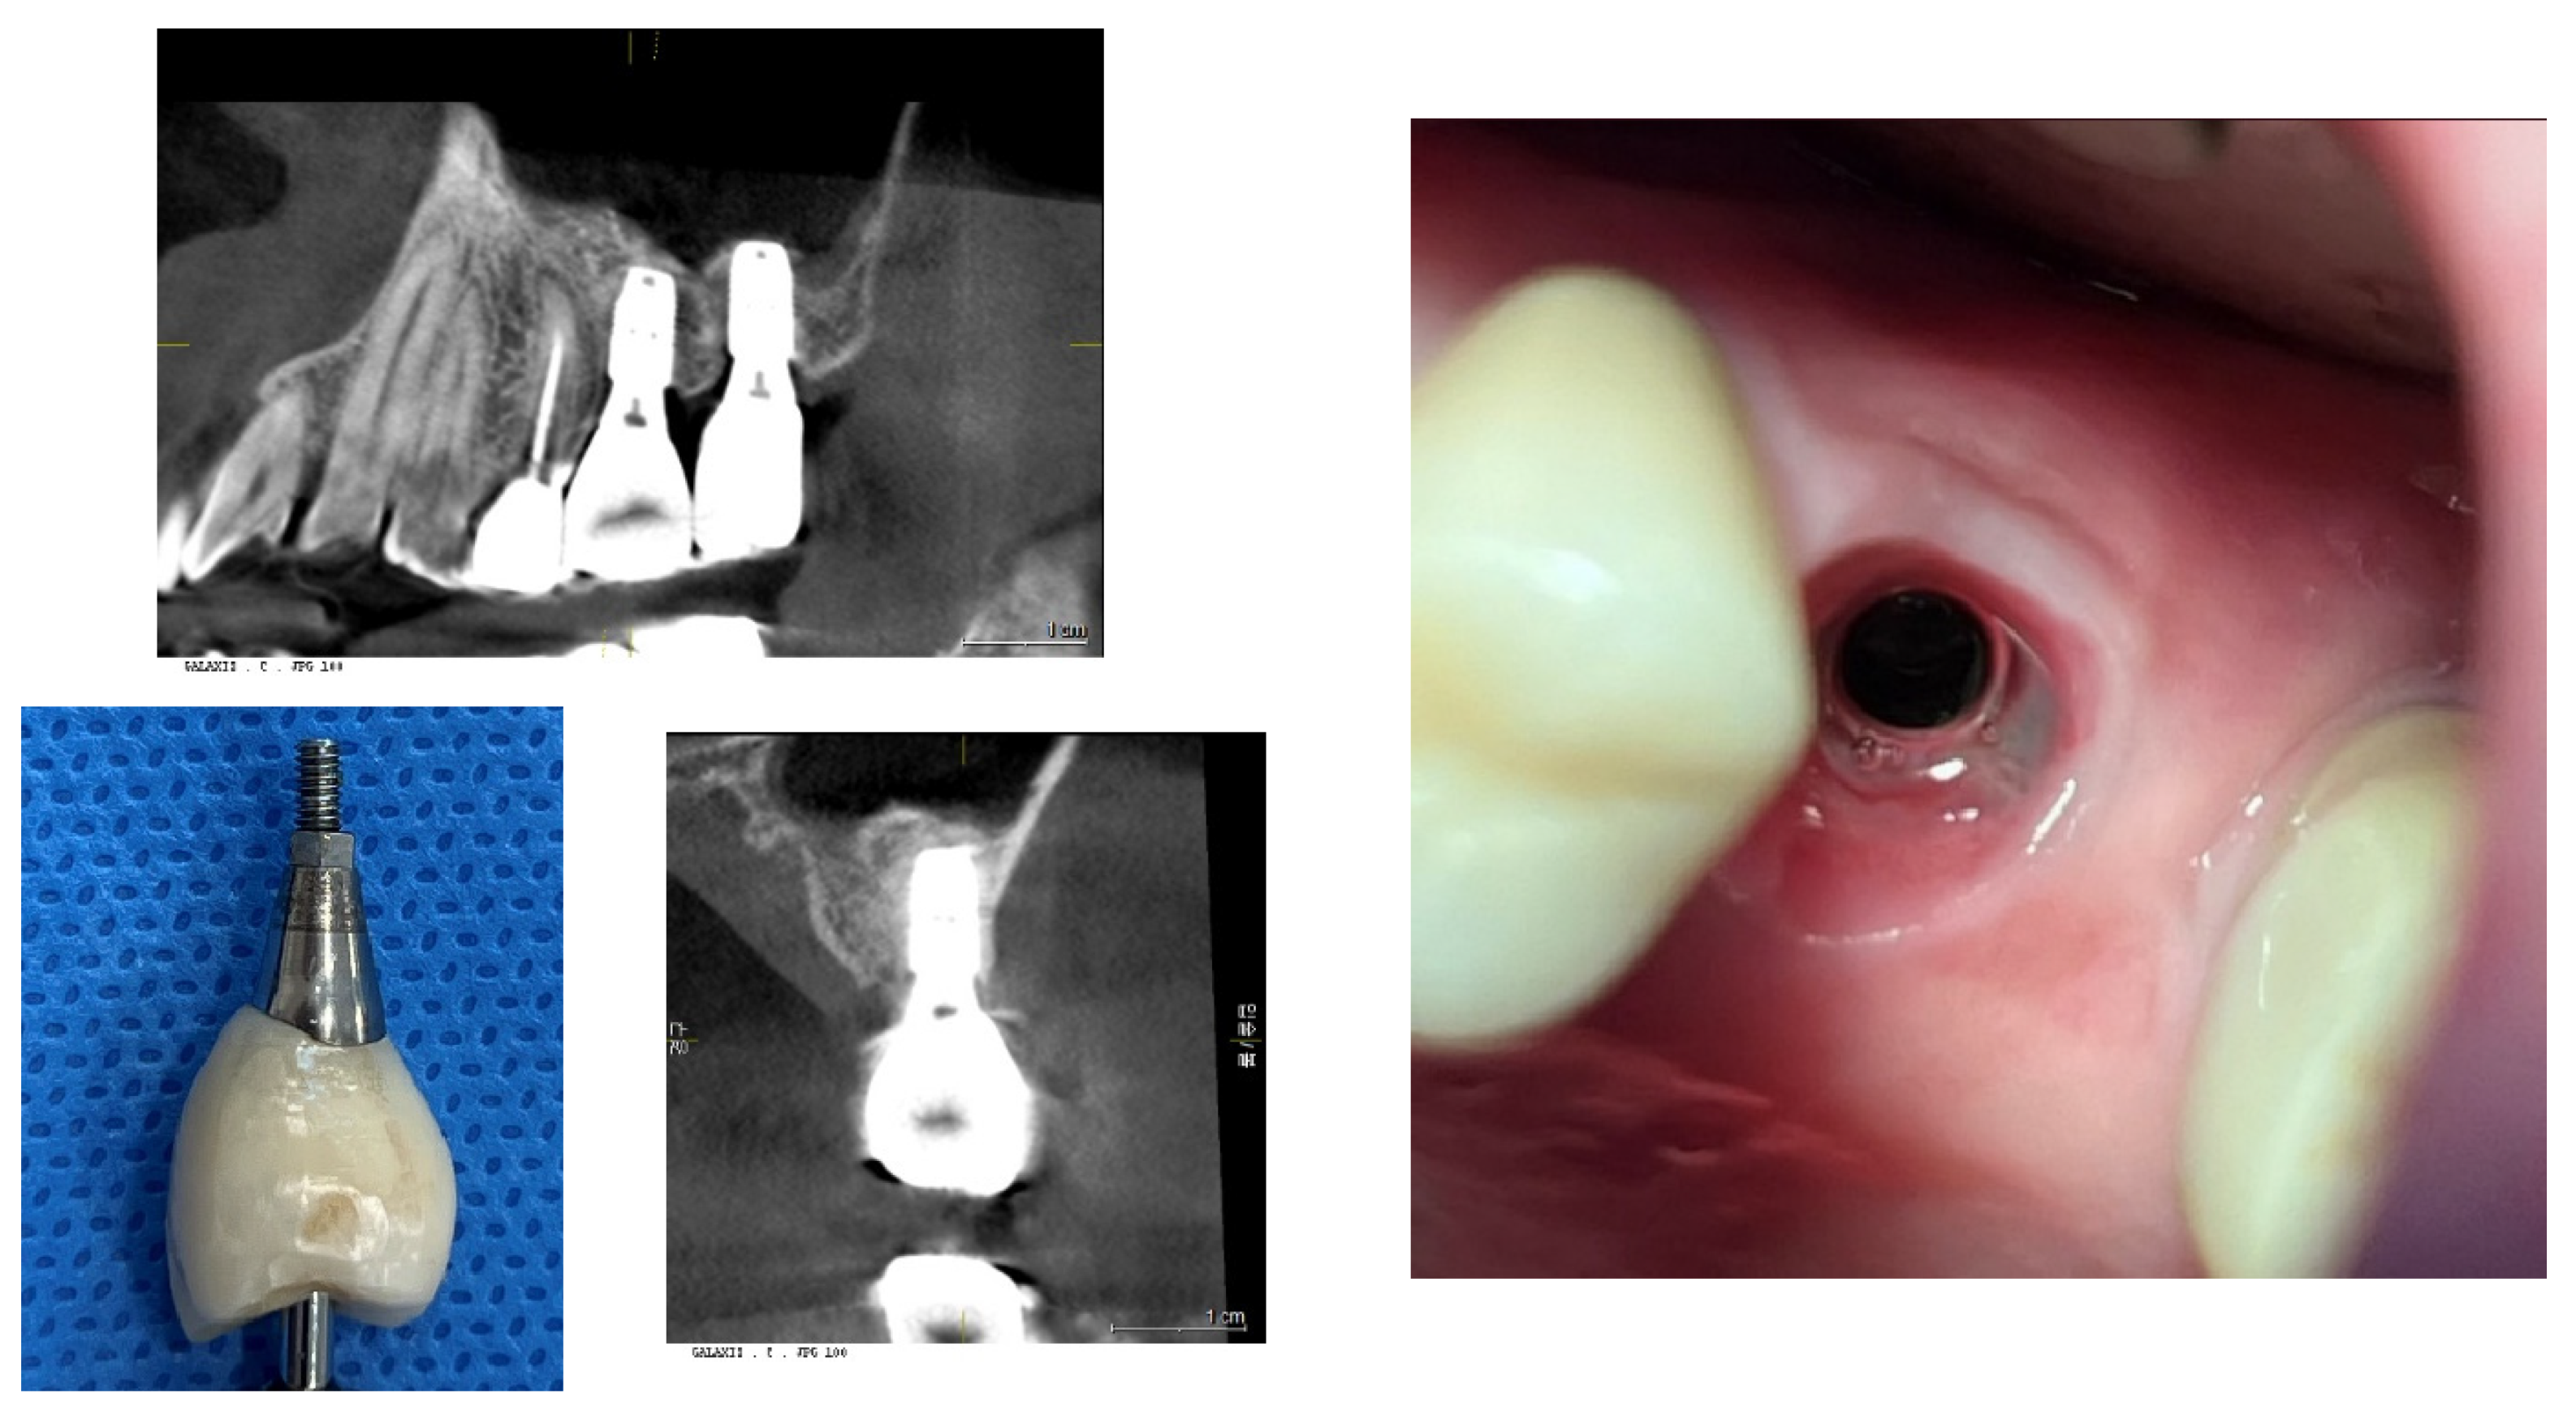

Figure 3 and Figure 4: Impact of Implant Placement Depth on Clinical Crown Shape

These figures demonstrate the effect of the depth of implant placement on the shape of the clinical crown. Figure 3 shows an equicrestal placement of a second molar implant, where insufficient vertical space necessitates a smaller diameter or an abrupt emergent profile for the clinical crown. In contrast, Figure 4 illustrates a subcrestal placement for a first molar implant, which provides sufficient vertical space allowing for the creation of a more natural-looking clinical crown with a gradual emerging profile.

Figure 3. Case Study of Epi-Crestal Placement of a Second Molar Implant. This figure illustrates a case where a second molar implant was placed epi-crestally, resulting in a smaller clinical crown size and an unnatural appearance due to an improper emergent profile compared to the adjacent natural molar. This outcome is attributed to the shallow depth of placement, which causes the transition part to be exposed supramucosally.

Figure 4. Comparative Case of Equicrestal vs. Subcrestal Implant Placement. This figure demonstrates the differences between equicrestal and subcrestal implant placements. For the implant in the position of the second molar, equicrestal placement results in a molar diameter reaching a short vertical distance, leading to an abrupt emergent profile with the transition part located supramucosally. In contrast, for the implant in the position of the first molar, subcrestal placement yields a more natural appearance, as it allows for a gradual emergence with the vertical distance matching the horizontal distance needed for diameter increase, and the transition part located submucosally.